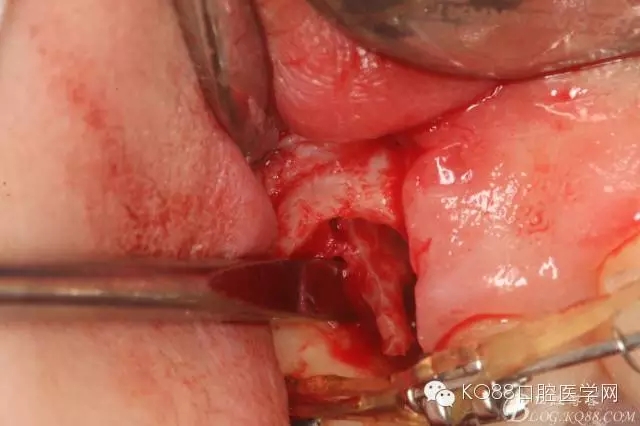

图11.仔细考虑之后,在14颊侧做垂直切口,切口长度仅达膜龈联合处,做小切口。

图12. 做垂直切口+龈沟内切口,形成角形瓣,暴露出15根面。